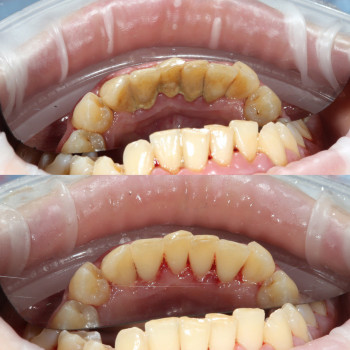

Лікування пародонтиту від 1 до 4 ступеня тяжкості у Хмельницькому Пародонтит – це запальне захворювання ясен і тканин, що утримують зуби. Без лікування воно прогресує від початкового нальоту й кровоточивості до серйозної втрати кісткової тканини та рухливості зубів. У нашій клініці ми проводимо комплексне лікування пародонтиту будь-якої стадії – від 1 до 4 ступеня тяжкості. ✔️ 1 ступінь – професійна гігієна, усунення нальоту, навчання догляду ✔️ 2 ступінь – кюретаж ясенних кишень, лікування запалення ✔️ 3 ступінь – комплексна терапія, шинирование, відновлення тканин ✔️ 4 ступінь – хірургічні методи, імплантація та протезування при втраті зубів Ми використовуємо сучасні методи: ультразвукову чистку, Air Flow, закритий кюретаж. Регулярне звернення до пародонтолога дозволяє зупинити прогресування хвороби, зберегти власні зуби та повернути здоров’я ясен. 👉 Запишіться на консультацію та лікування пародонтиту у Хмельницькому – відновіть здоров’я ротової порожнини на будь-якій стадії захворювання!